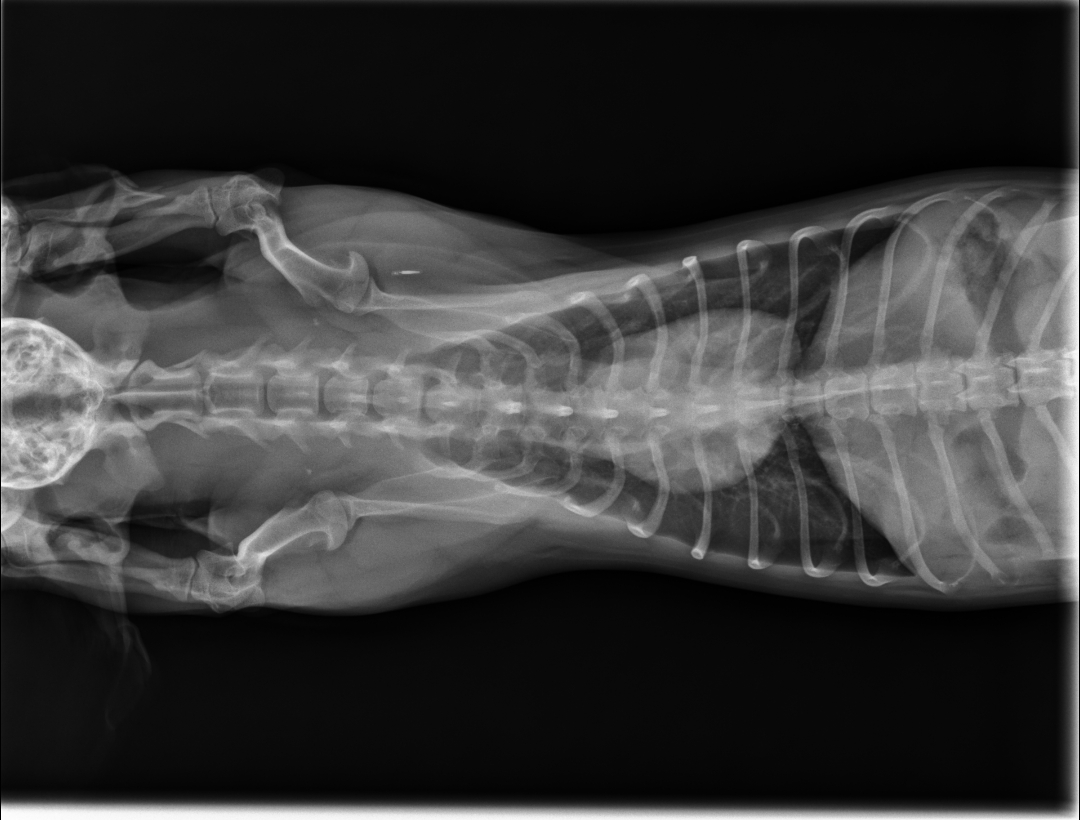

- De lister les facteurs limitants de la radiographie

- D’expliciter le choix des constantes et du matériel

- De décrire les incidences standards chez les petits mammifères

- De lister les particularités anatomiques dominantes chez les chez les petits mammifères les plus communs

- D’identifier les organes visibles sur une radiographie de petit mammifère